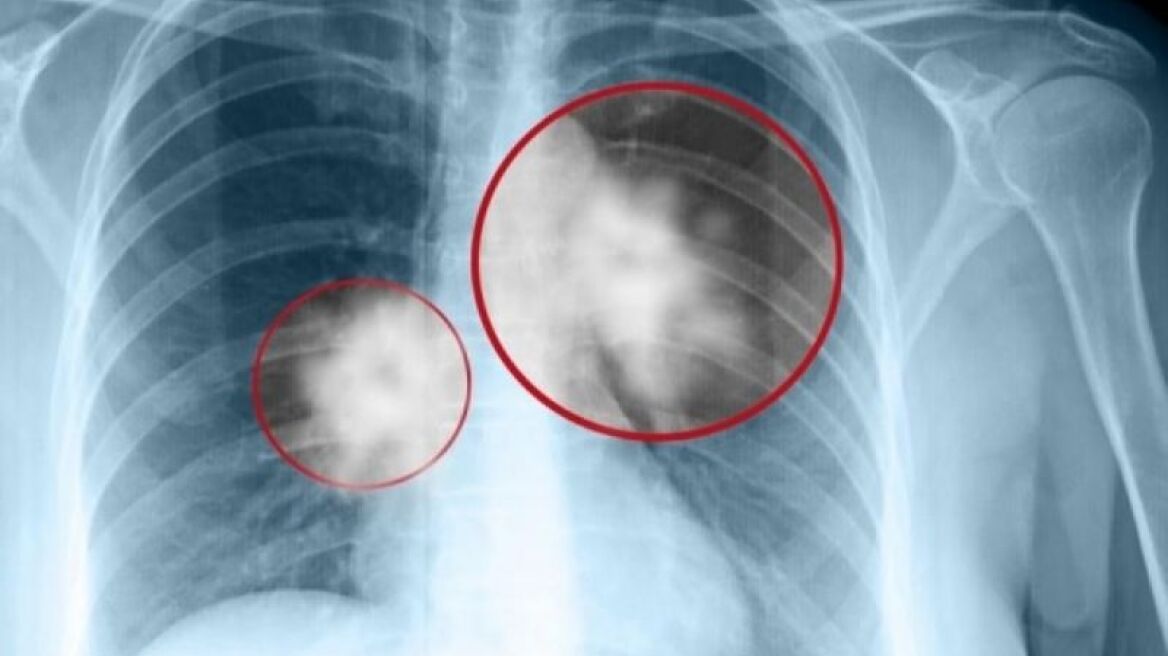

Μια επαναστατική τεχνική, που συνδυάζει τα χαρακτηριστικά του υπερήχου και της ενδοσκόπησης, αποτελεί η ενδοβρογχική υπερηχογραφία EBUS-TBNA, η οποία συμβάλει στη διάγνωση και σταδιοποίηση του καρκίνου του πνεύμονα, της σαρκοείδωσης, του λεμφώματος, των μεσαυλικών λεμφαδενικών μεταστάσεων, κ.α.

Εξηγώντας τη λειτουργία της αναφέρει: "Με τη βοήθεια των υπερήχων μπορούμε πλέον με το κοινό βρογχοσκόπιο να δούμε και έξω από τους βρόγχους, τους πνεύμονες και μπορούμε να πάρουμε βιοψία επιλεκτικά από παθολογικές καταστάσεις, από όγκους , από οτιδήποτε διηθήσεις, σκιές κλπ των πνευμόνων που μέχρι τώρα δεν μπορούσαμε να πάρουμε. Η ενδοβρογική υπερηχογραφία, που τα τελευταία χρόνια έχει δώσει επανάσταση κυρίως στην έγκαιρη διάγνωση του καρκίνου του πνεύμονα, αυτή τη στιγμή λειτουργεί στο Ιατρικό Διαβαλκανικό και στο Ιατρικό Αθηνών με μεγάλη επιτυχία".

Η ενδοβρογχική υπερηχογραφία έχει φέρει επανάσταση στην έγκαιρη διάγνωση του καρκίνου του πνεύμονα, στη σταδιοποίηση του καρκίνου (η οποία είναι πολύ σημαντική σε ό,τι αφορά το αν ο καρκίνος μπορεί να χειρουργηθεί ή όχι και να ακολουθηθεί η κατάλληλη θεραπεία) και στον προσδιορισμό του καρκίνου του πνεύμονα μετά τη θεραπεία, προσθέτει ο κ. Τιτόπουλος.